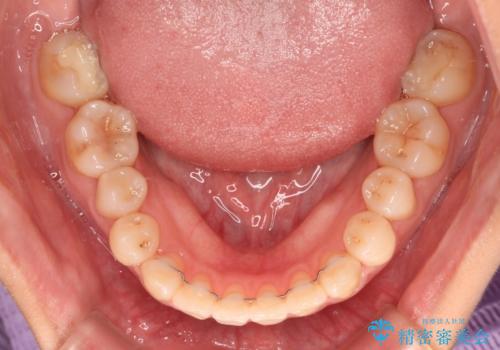

クロスバイト改善まではスムーズに進みましたが、その後は強い舌の突出癖によりオープンバイトの期間が長く続きました。

舌のトレーニングをしっかりと実施してもらい、何とか仕上げることができました。